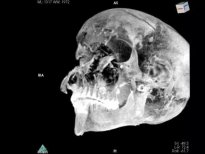

Korkunç gerçek, firavunun tomografisinde ortaya çıktı

Mısır firavunu Seqenenre Taa II (Seqenenre Tao II olarak da yazılır), yaklaşık M.Ö. 1558 yıllarında güney Mısır'ın hükümdarıydı. MÖ 1553'te Hiksoslar tarafından Mısır'ın işgali sırasında savaşta hayatını kaybetti.

Mısır firavunu Seqenenre Tao'nun mumyası bilgisayarlı tomografiye sokuldu.